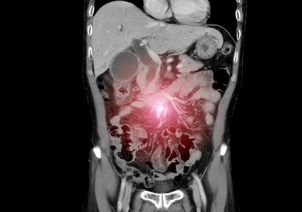

4. 장폐색 & 장유착, 어떻게 진단하나요? 영상 검사와 혈액 검사

장폐색과 장유착은 환자의 증상, 병력, 신체 검사 결과를 종합적으로 고려하여 진단합니다. 복부 X-ray, CT, MRI 등 영상 검사를 통해 장 폐쇄 부위와 원인을 확인하고, 혈액 검사를 통해 염증 수치, 전해질 불균형 등을 확인합니다.

- 복부 X-ray: 장 내 가스 분포를 확인하여 장 폐쇄 여부를 진단합니다.

- CT (컴퓨터 단층촬영): 장 폐쇄 부위와 원인을 더욱 정확하게 확인할 수 있습니다.

- MRI (자기공명영상): CT보다 연부 조직을 더욱 자세히 볼 수 있어 장유착 진단에 유용합니다.

- 혈액 검사: 염증 수치 (백혈구 수치, CRP 등), 전해질 불균형 등을 확인합니다.